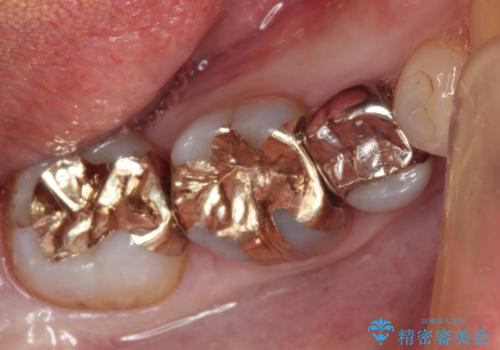

ゴールドインレーは適合がよいため、虫歯の再発のリスクが少ない非常に優れた材料です。

ゴールドインレーはセラミックインレーと比べ、割れるリスクが低いため、咬合力が強い方にお勧めです。